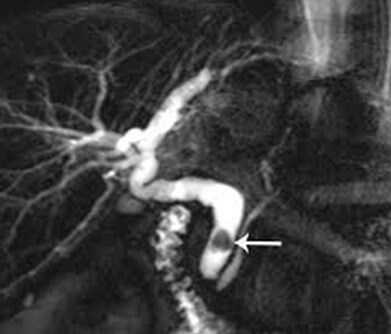

Магнитно-резонансная томография позволяет увидеть внутри- и внепеченочные жёлчевыводящие протоки, а также главный панкреатический проток. К этому методу диагностики прибегают при подозрении о наличии конкрементов в общем жёлчном протоке. Это необходимо для планирования лечения.

На рисунке стрелкой обозначен конкремент в общем жёлчном протоке. При помощи дуоденоскопа в двенадцатиперстной кишке выполнено рассечение сфинктера Одди. Введено рентгеноконтрастное вещество, позволяющее визуализировать конкремент. При помощи специальной корзинки, выполняется захват и извлечение конкремента.